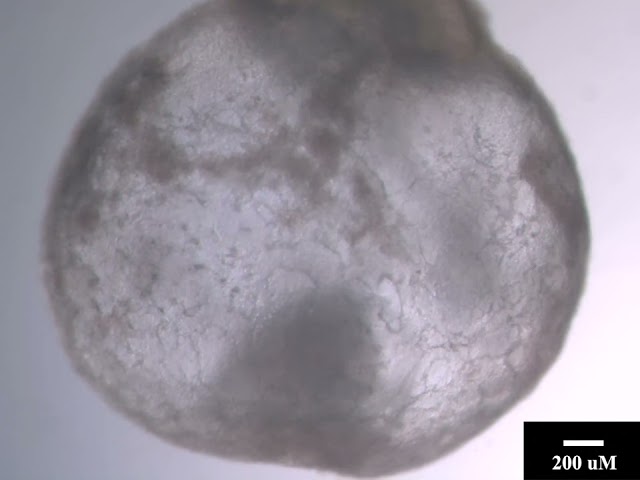

Scientists in Israel are now one step closer to growing human organs in a laboratory thanks to mouse embryos. They successfully grew synthetic mouse embryos without using sperm, eggs, or a womb. Instead, they used stem cells and an artificial womb. Fifty of the 10,000 trials were successful, with the longest lasting eight days into embryo development. Full mouse pregnancies usually last 20 days. Despite the failure rate, it’s a huge leap in the long process of optimizing stem cells to treat human diseases.

The peer-reviewed journal Cell published the data. The researchers from Weizmann Institute of Science are the same team that published designs for an artificial womb in 2021. They used the same device in this experiment. The mechanical womb setup is transparent so they can study and document every step of the process. It is also being further developed by Renewal Bio, a company co-founded by the lead author of the studies, Jacob Hanna.